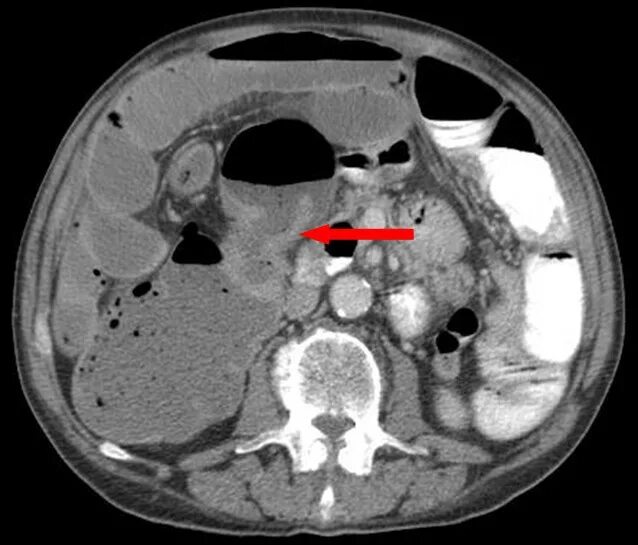

Рак прямой кт